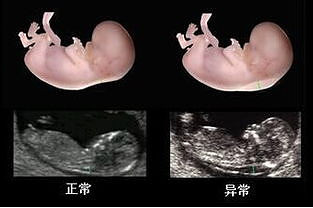

★问题二:产检时,医生没让我去做NT,那么NT到底有没有必要做,最适合做NT的时间是什么时候,错过了时间,做了还有意义吗?

✎解答➱NT筛查是颈部透明带厚度,早期的排查畸形的项目,有助于检查胎儿的健康状况。检查时间一般为11周-13+6周之间,最佳的时间为12周。因为在这段时间98%-100%可测量NT的厚度,而14周则降至11%。有研究发现NT值在3mm时,90%为正常胎儿,10%为异常胎儿;而NT值达到6mm时,90%为异常胎儿。所以一般医生都会认为NT值在2.5mm以内都算是正常的。但是这项检查有些医院是没有做的,孕妈咪在产检的时候如果医生没有开NT项目的检查单,可以咨询下医生,或是去别的医院做这项检查都是可以的。